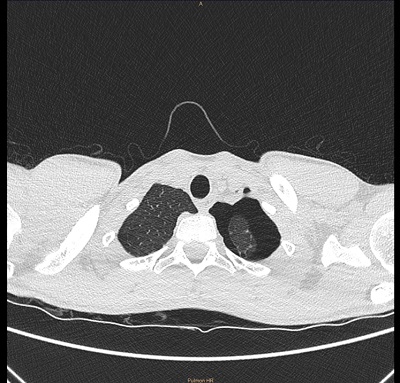

Ante el dolor pleurítico y la sospecha de neumotórax se deriva al centro hospitalario de referencia para la realización de una radiografía torácica; tras la cual se confirma la sospecha clínica (Fig. 1). El paciente ingresa durante 48 horas, permaneciendo asintomático y con una radiografía al alta con persistencia del neumotórax y controles por cirugía pediátrica y neumología infantil.

| Figura 1. Radiografía de tórax anteroposterior. Neumotórax izquierdo de localización apical con un grosor máximo de 2 cm |